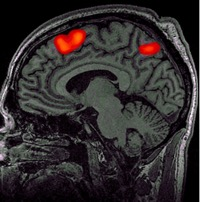

While significant advancements in artificial intelligence (AI) have catalyzed progress across various domains, its full potential in understanding visual perception remains underexplored. We propose an artificial neural network dubbed VISION, an acronym for "Visual Interface System for Imaging Output of Neural activity," to mimic the human brain and show how it can foster neuroscientific inquiries. Using visual and contextual inputs, this multimodal model predicts the brain's functional magnetic resonance imaging (fMRI) scan response to natural images. VISION successfully predicts human hemodynamic responses as fMRI voxel values to visual inputs with an accuracy exceeding state-of-the-art performance by 45%. We further probe the trained networks to reveal representational biases in different visual areas, generate experimentally testable hypotheses, and formulate an interpretable metric to associate these hypotheses with cortical functions. With both a model and evaluation metric, the cost and time burdens associated with designing and implementing functional analysis on the visual cortex could be reduced. Our work suggests that the evolution of computational models may shed light on our fundamental understanding of the visual cortex and provide a viable approach toward reliable brain-machine interfaces.